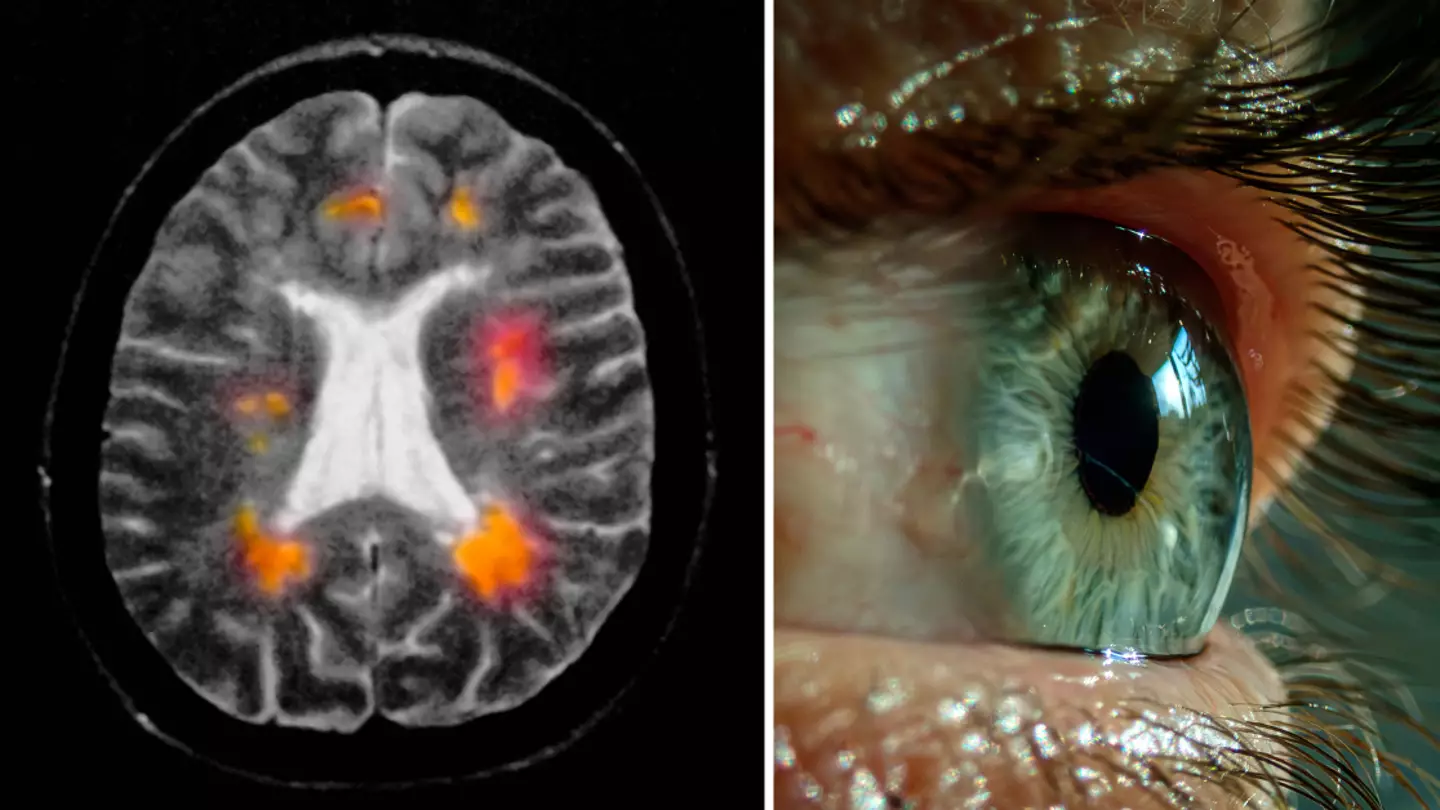

There are early symptoms of Multiple Sclerosis that can be found in the eye, according to experts who have claimed it is 'unpredictable'.

Multiple Sclerosis (MS) is a chronic, inflammatory, autoimmune disease which can develop in any part of the body.

MS attacks the central nervous system, meaning there can be damaged nerves that disguise as other symptoms/conditions.

Neurologist and MS expert Thomas Shoemaker spoke to Rush, and explained: "Because MS can develop anywhere within the central nervous system and encompasses the optic nerves, the brain and the spine, a lot of different types of critical attacks can occur, so that leads to diagnostic complexity."